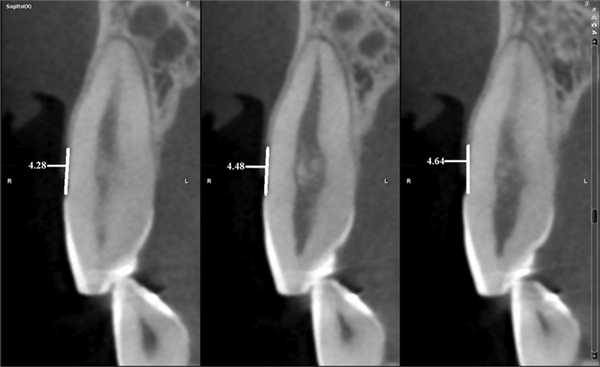

Для повышения точности исследования проводили 3 вестибуло-оральных реформата относительно центральной оси с шагом 0,5 мм.

Рис. 6. Измерение расстояния от ЭЦГ до альвеолярного гребня в области зуба 1.3 (клиническая рецессия — 1,6 мм). В данном случае показатели на 3 реформатах составили: 4,28; 4,48; 4,64 мм.